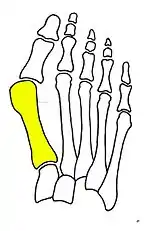

Fibrous connecting bridge to prevent recurrence

Fig. 3: Fibrous connecting bridge to prevent recurrence

Syndesmosis procedure addresses specifically the two fundamental problems of metatarsus primus varus deformity that gives rise to the bunion deformity. They are leaning and instability of the first metatarsal bone . Syndesmosis procedure uprights the leaning first metatarsal bone with strong binding sutures between it and the second metatarsal bone (Fig. 2) and then also stabilizes it uniquely by creating a fibrous connecting bridge between these two bones (Fig. 3, 4). First metatarsal bone can be readily realigned because by definition of the metatarsus primus varus deformity its first metatarsal is abnormally loose and mobile.